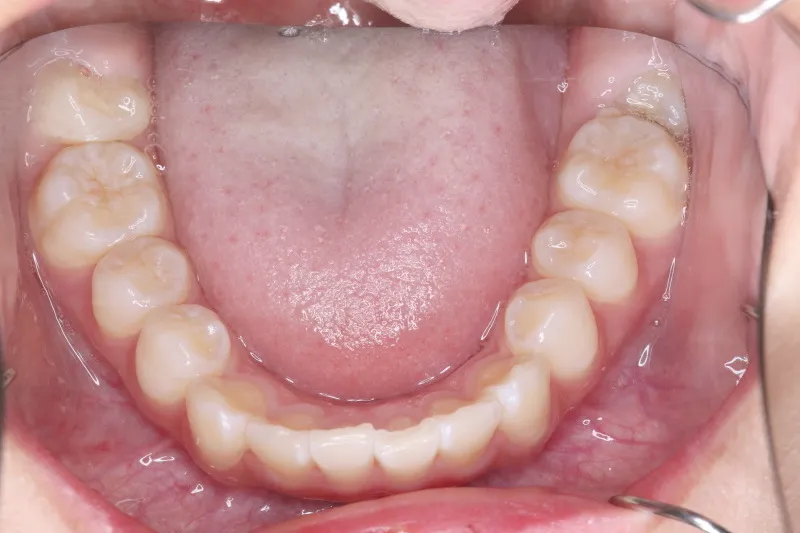

治療終了後

治療回数43回、7年4ヶ月の治療期間で矯正治療を終了しました。

主訴が改善され、ご満足頂きました。